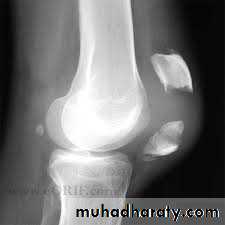

Tibial plateau fractures:

Direct blow or fall from height may cause fracture of one tibial condyle or both.

Fracture lateral condyle is the commonest named as bumper fracture

caused by a force that abducts the tibia upon femur while the foot is fixed on ground.

Patient usually is an adult, the knee joint is swollen, bruises, there is diffuse tenderness and doughy feel of haemarthrosis.

ligaments injuries must be excluded.

Imaging : X-ray

: anteroposterior, lateral & oblique views.

CT -Scan may used to detect amount of depression and comminuation.

Tibial plateau fracture